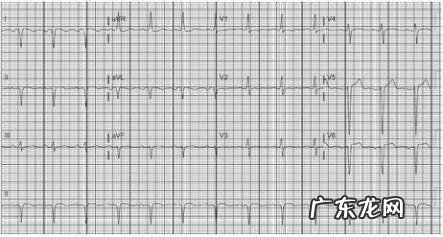

心内科门诊来了30岁年轻男性,很是焦虑,说自己刚体检做了心电图(图1),被告知得了心肌梗死,而且很严重,要求立即转诊三甲医院 。

图1:患者体检心电图,多导联主波负向,怀疑“心肌梗死” 。

于是为患者复查心电图(图2),发现之前的心电图异常都消失了,进一步完善超声心动,心脏结构和功能均未见明显异常 。至此恍然大悟,患者原来的心电图因出现了多导联的Q波,胸前导联R波递增不良,而被诊断为心肌梗死,而这一切的原因,都是肢体导联和胸导联接反了 。

图2:调整左右手及胸导联顺序后,心电图恢复正常 。

仔细对比图1和图2发现,图1中出现了I导联主波向下,aVR导联主波向上的情况,这便提示存在左右手接反的可能 。图1中的II导联和图2中的III导联图形类似,图1中的aVL导联和图2中的aVR导联类似,也印证了左右手接反的猜想 。

图1中V1导联和图2中V6导联图形类似,图1中V6导联和图2中V1导联图形类似,说明胸导联从左至有也完全接反了 。

在临床中,如碰到这种莫名奇妙的“心梗”,不能解释的电轴严重偏移或aVR导联主波向上,以及胸前导联R波递增顺序明显异常,需考虑到导联接反的情况,以免导致误诊和不必要的检查 。